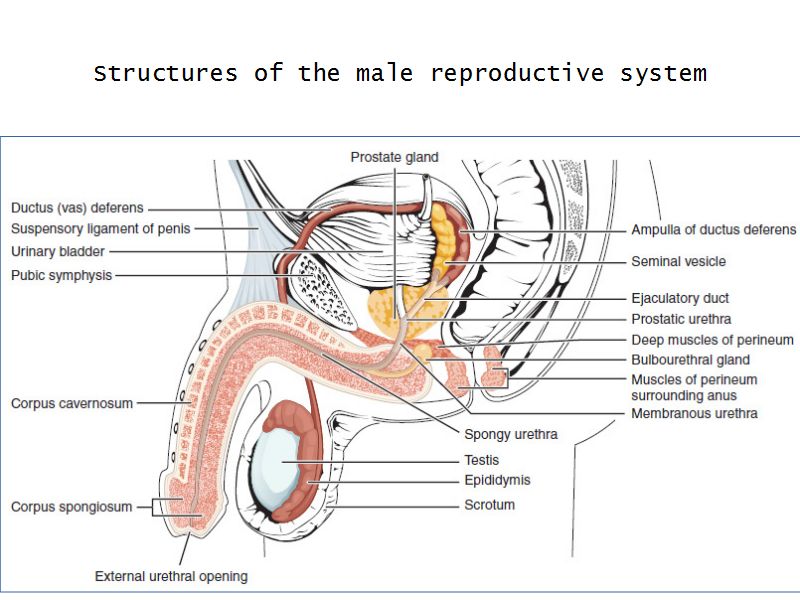

Testis

Slide 84

Testis

- Tunica albuginea

- Lobuli

- Seminiferous tubuli

- Epididymus

- Ductus deferens

Tunica albuginea

- Thick fibrous CT capsule

- Forms septae

- Divide testis into lobuli

Lobuli

- Pyramidal shaped compartments

- Contain 1 - 4 seminiferous tubules each within

- Meshwork of loose CT

- AVN

- Leydig cells

Leydig cells

- Interstitial cells

- Surrounded by rich AVL

- Large round - polygonal shape with clear cytoplasm

- Large central nucleus

- Endocrine - testosterone

Ductus deferens

Also vas deferens

Penis

Slide 83Penis

- 3 cylindrical masses erectile tissue

- 2x corpora cavernosa

- 1x corpus spongiosum

- Surrounded by tunica albuginea

- Covered by skin

- Traversed by urethra